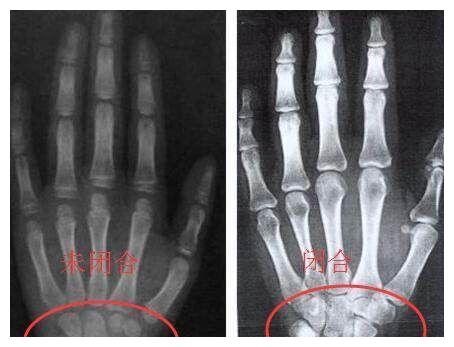

骨龄是骨骼年龄的简称 通常要拍摄左手手腕部的x光片 医生通过

孩子比同龄人矮很多时,这个检查很有必要做!

(正常手骨x光片)